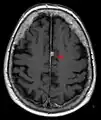

T1 (note CSF is dark) with contrast (arrow pointing to meningioma of the falx)